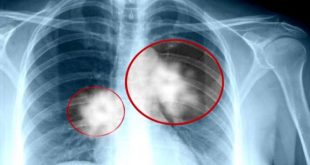

باحثون يتوصلون إلى طريقة لعلاج نوع من سرطان الرئة

بكين-سانا توصل باحثون صينيون إلى طريقة جديدة في علاج نوع شائع من سرطان الرئة وذلك بمكافحة الجين الذي يؤدي إلى هذا النوع من السرطانات. ووفقا للدراسة التي أجراها باحثون من معهد خفي للعلوم الفيزيائية التابع للأكاديمية الصينية للعلوم فإن للجين …